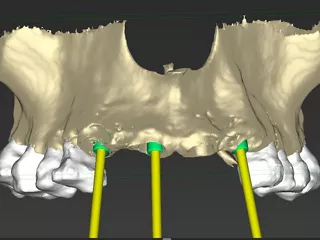

• CBCT préopératoire avec plan des implants